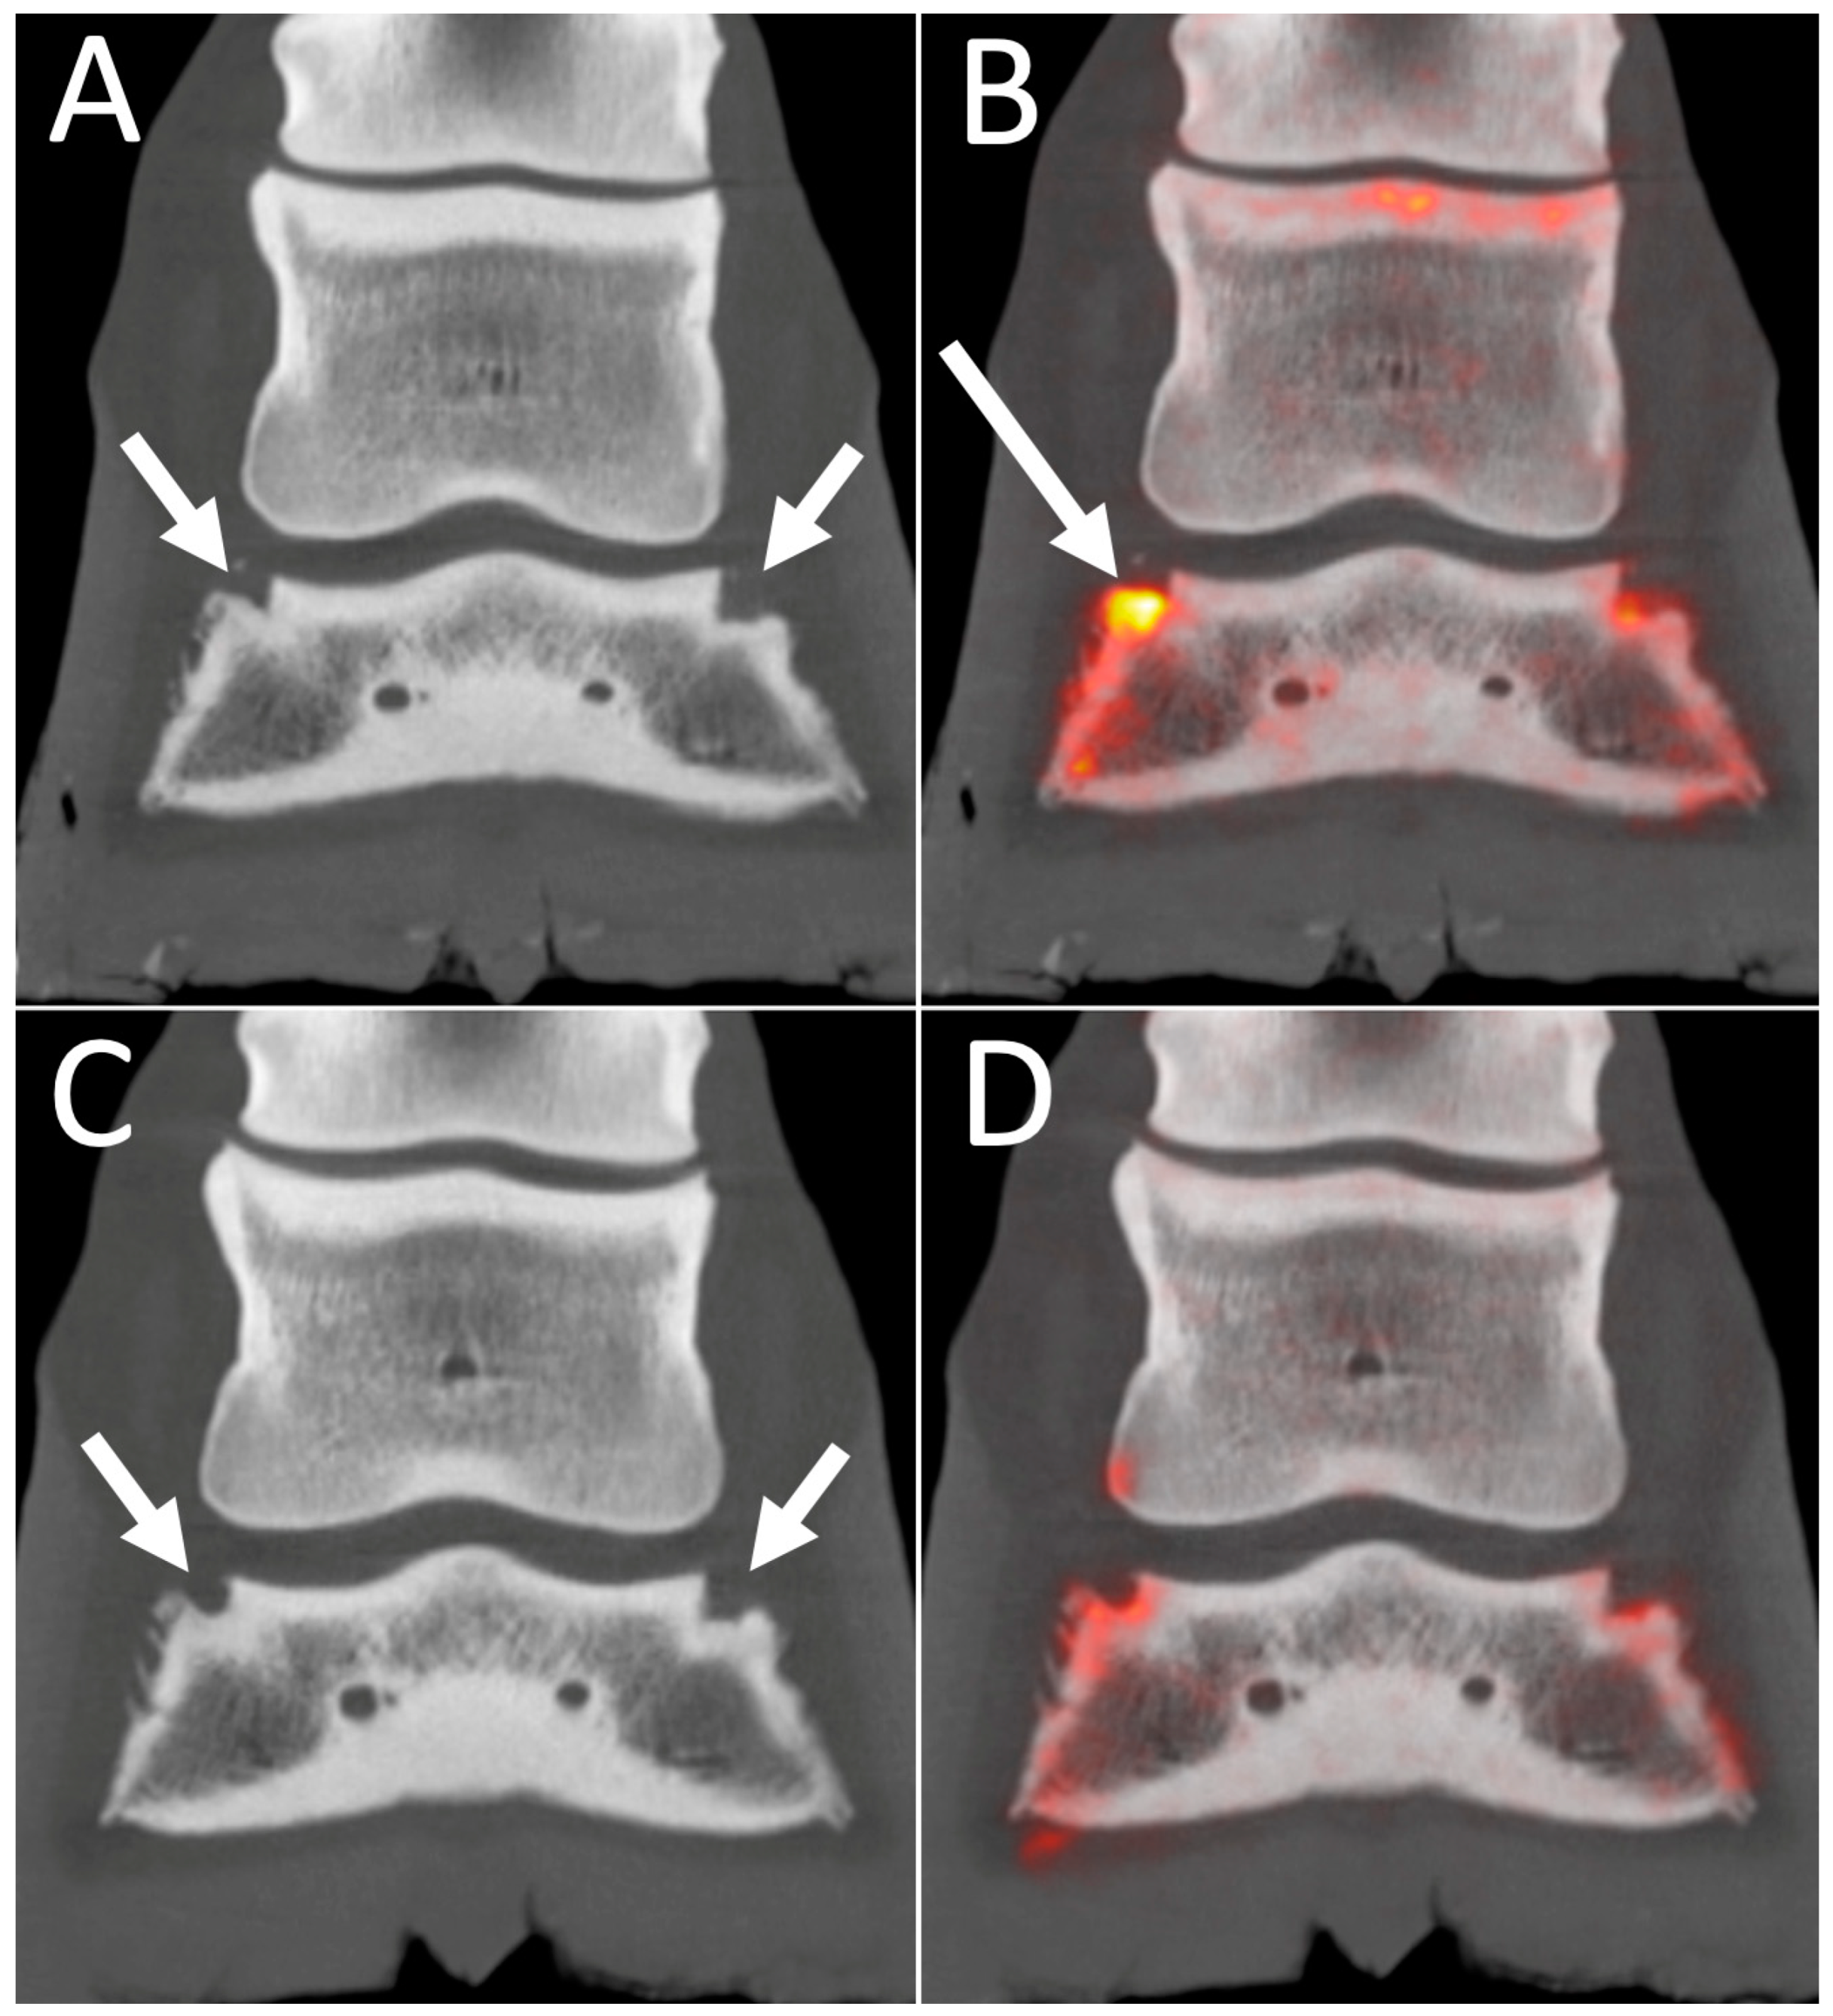

4.2. 18F-NaF PET Combined with CT or MRI for Optimal Bone Imaging

4.4. PET for Longitudinal Monitoring of Lesions